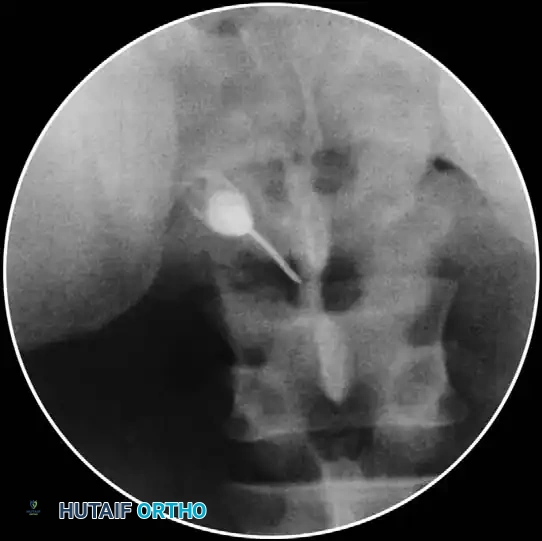

3. Localization: Using anteroposterior (AP) fluoroscopic imaging, identify the target laminar interspace.

- Aspiration and Contrast: Aspirate to ensure no CSF or blood return. Attach a 5-mL syringe containing 1.5 mL of nonionic contrast dye (e.g., Iohexol).

- Epidurogram Confirmation: Inject the contrast under live fluoroscopy to produce an epidurogram. Adjust the C-arm to a lateral perspective to definitively document posterior epidural spread and rule out intrathecal or intravascular flow.

- Test Dose and Injection: Inject a test dose of 1-2 mL of 1% preservative-free lidocaine. Wait 3 minutes. Monitor for signs of spinal anesthesia (apnea, profound paresthesias). If negative, slowly inject a mixture of 2 mL of 1% lidocaine and 2 mL of Celestone Soluspan (6 mg/mL).

- Contrast Flow: Remove the stylet. Aspirate vigorously. Inject 0.5 mL of nonionic contrast under live fluoroscopy. You must observe filling of the oval neuroforamen and distal flow along the exiting nerve root. If rapid vascular washout is seen, abort the procedure immediately.

- Contrast Injection: Live fluoroscopy during contrast injection must demonstrate medial flow into the epidural space and lateral flow outlining the exiting spinal nerve.